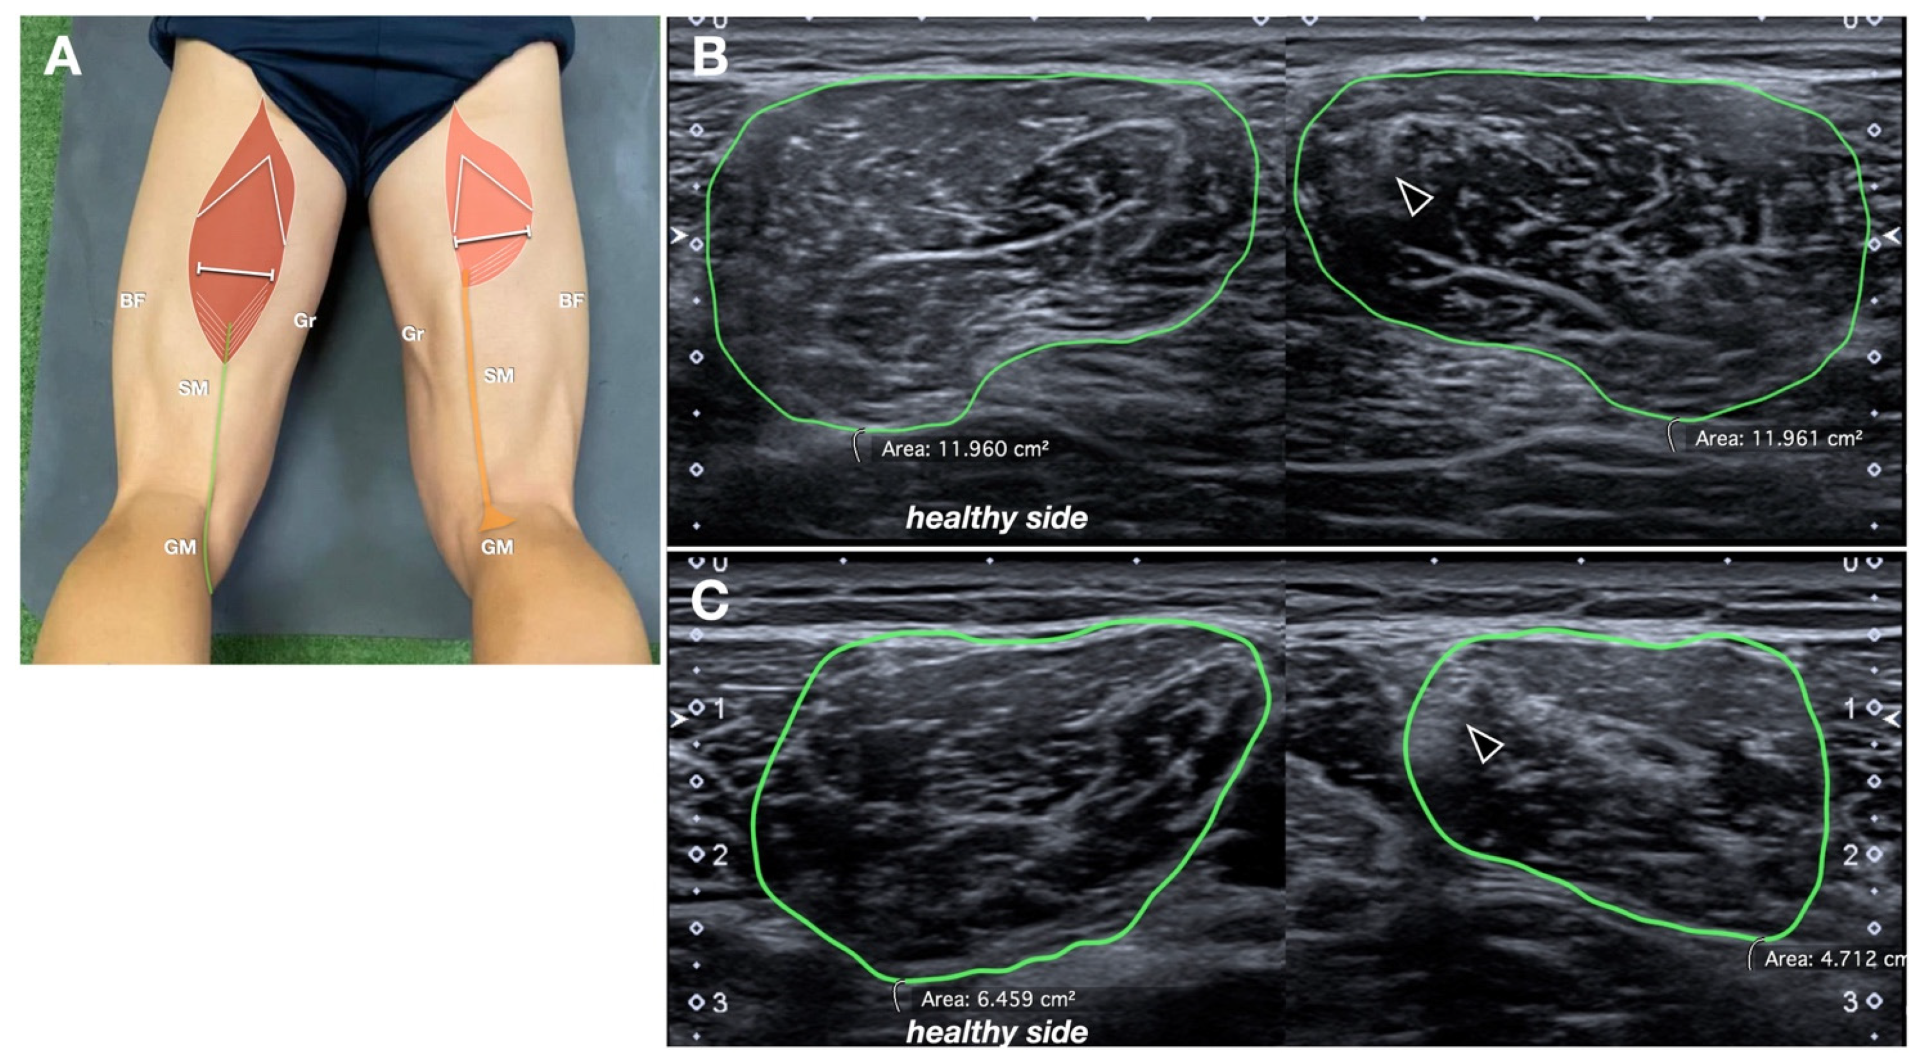

The cross-sectional area (CSA) of the ST muscle belly was measured bilaterally, at the middle third of the thigh, using axial sonograms, with measurements compared to the contralateral side (Figure 6). To ensure reproducibility, the CSA was measured at the level where the intramuscular raphe of the ST, a reliable anatomical US landmark for the identification of the muscle, was no longer visible (just caudal to it) [14]. The muscle CSA ratio was calculated similarly to the tendon CSA ratio.

Figure 6. Semitendinosus muscle CSA ratio. (A) Schematic drawing (same as Figure 1B, refer to it for the abbreviations) indicating probe position. (B,C) Comparative axial sonograms in two different patients. The margins of the semitendinosus muscles are manually traced (in green) to obtain the corresponding CSA. In (B), the CSA is similar between the two sides, with only some mild echostructural alteration along the intramuscular tendon (black arrowhead) of the semitendinosus muscle. In (C), the CSA is reduced more evidently.